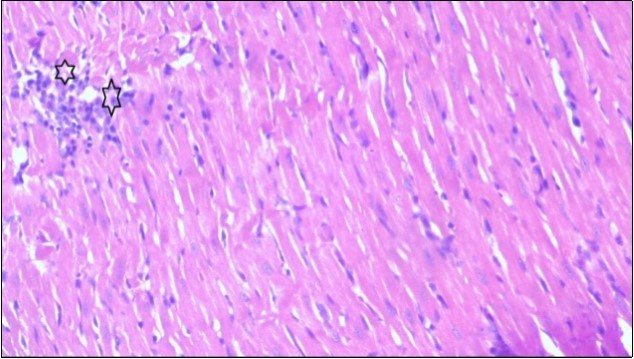

An important organ that is affected directly by the obesity which is the heart: The heart is the main important organ in circulatory system, the heart wall has three basic layers; the tunica intima of the heart is called endocardium, the tunica media of the heart is called the myocardium, the tunica adventitia of the heart the epicardium. The histological examination of the hearts of control rats feeding standard diet showing normal cardiac tissue with elongated, unbranched multinucleated muscle fibers (arrow), (Figure 1). The rats are feeding (HFD) for 2 weeks (obese rats) showing large number of inflammatory cells (star), degeneration muscles fiber ,circle and congested Blood vessels (arrow) (Figure 2). By comparison hearts of rats are treated by fennel after obesity and control rats observed show improved cardiac tissue with less infiltration (star) and well organized elongated muscle fibers with peripheral nuclei (arrow) (Figure 3). While examination of rats heart that treated by ator after obesity appears show less improved cardiac tissue with few inflammatory cells between disorganized muscle fiber (star), (Figure 4). While combined hearts of rats are treated by fennel and ator after obesity and control mice are showing nearly cardiac tissue with well-organized muscles fibers (arrow), (Figure 5).

Figure 5.Photomicrogragh of heart section of treated rat with both fennel herb and Ator drug showing nearly normal cardiac tissue with well-organized muscles fibers (arrow), (H&E) (400X).

These results were confirmed with histological changes of feeding rats heart tissues with high fat diet only, which showed vaculation of tunica media and narrowing in the lumen of aorta sections as well as congestion of cardiac blood vessel and hyalinosis of its wall. This result was confirmed by Szilvassy et al., 78, who indicated that although hyperlipidemia increases oxidative stress in the cardiovascular system, it renders the heart and the vasculature more susceptible to stress. Ouwens et al. 79 identified that development of hyper-cholestremia, which is one of the risk factors for cardio vascular diseases is associated with increased blood levels of TC, LDL-C and VLDL-C as well as lowered levels of HDL in rats fed on high fat-diet. This result was confirmed by histological study, which revealed apparent normal histological structure of heart in all treated rats with fennel seeds. Epidemiologic studies have shown an inverse correlation between HDL-C level and the risk of cardiovascular disease. Increasing the HDL cholesterol level by 1mg may reduce the risk of cardiovascular disease by 2 to 3 percent 80. The present data agreed with Fatiha et al. 81, who reported that hyper-lipidemic rats treated with fennel extract had significant decrease in plasma levels of TL, TG, TC, LDL-C and VLDL, and significant increase in HDL-C level. The current study demonstrates that the alteration induced by high fat diet causing changes in blood parameters. These changes are exhibited through a decrease in RBCs, Ht, Hb and platelet and these changes could be due to oxidative stress, which lead to lipid peroxidation in RBCs membranes, auto oxidation of hemoglobin. As regards the total WBCs, lymphocytes and monocytes showed a marked decrease. While a distinct increase in the percentage of neutrophils and esinophils. The present, demonstrates that rats treated with (fennel), (ator) and (fennel with ator) exposure provided significant protection to the altered haematological variables. The effect of the treatment with fennel and ator is more effective than fennel only or ator only. The current study showed that the serum levels of the total protein and albumin in the obese group were significantly higher than those of the control group. The administration of (fennel) revealed significant decrease in the serum levels of the albumin and total protein as compared to the obesity group, although the serum levels of the albumin and total protein of the Ator group less than the obesity group. Otherwise, the levels of the total protein and albumin in fennel and Ator group were near to the similar value of the control group. The finding of this study indicates that the concentration of Malondialdehyde (MDA) and Myeloperoxidase (MPO) in liver homogenates of the fennel and ator group significant decrease than group (3) and group (4) and obesity group. There is a growing awareness that obesity is a prime risk factor for the development of dyslipidemia profile and that oxidative stress may play a role in various adverse effects of obesity.